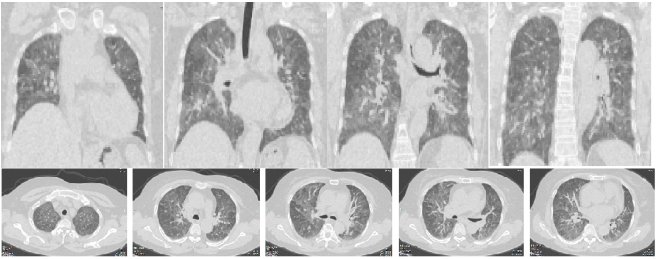

患者女性,57岁,退休会计,因“间断性发热伴咳嗽2年余,再发伴胸闷5天”于2017年11月9日入院。患者2年内无明显诱因出现反复发热3次,急性起病,伴流涕、咳嗽、胸闷、活动后气喘,查体见口唇发绀,双肺闻及少许湿啰音,血气分析提示Ⅰ型呼吸衰竭,需吸氧,无创/有创机械通气治疗,对抗生素应答不佳,静脉应用糖皮质激素后症状可在5~7 d内迅速好转。末次起病时胸部CT如图1所示。

图1  病例1就诊时胸部CT

完善肺功能检查提示弥散功能降低,支气管镜检排除其他疾病,疑诊过敏性肺炎,追问病史,患者生活环境为一楼,较为潮湿,卧室有霉变墙壁及家具。符合过敏性肺炎的临床诊断标[2]。针对过敏性肺炎治疗后症状迅速好转,顺利出院,嘱患者清理霉变家具,脱离环境。定期随访,未再出现咳嗽、胸闷、气喘症状。出院时胸部CT见图2。

图2  病例1出院时胸部CT